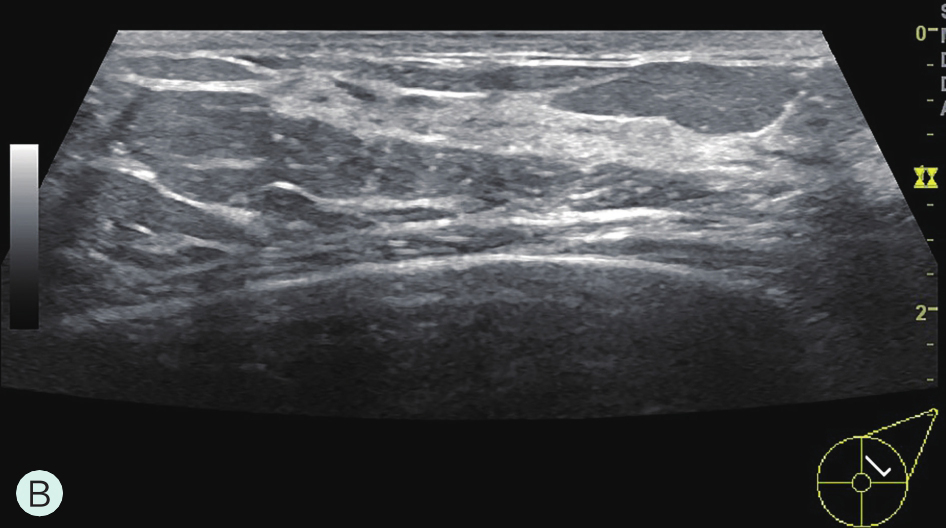

图1-3-2 乳腺超声不同乳腺密度

A.脂肪型;B.散在致密型;C.不均匀致密型;D.极度致密型

B级:散在纤维腺体致密型(图1-3-1B、图1-3-2B、图1-3-3B)。